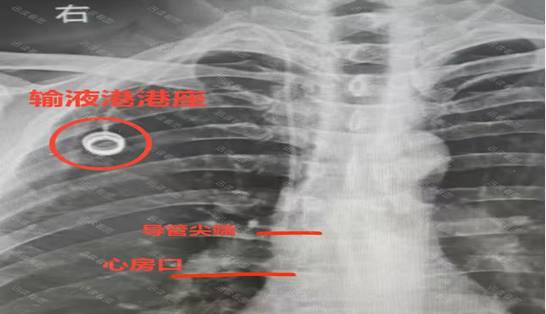

近日,重庆中医药学院附属九龙坡医院外科(普外)冶金村院区静疗团队与胃肠外科团队协同发力,成功开展“深静脉置管导管尖端心电定位术引导下胸壁静脉港置入术”与“局麻下经皮胃穿刺造瘘术”两项新技术,为两名特殊需求患者打通“生命通路”,标志着科室在肿瘤患者血管通路建立与营养支持治疗领域实现新突破。精准导航,为化疗患者筑牢“生命港湾”一位正在接受膀胱癌化疗的患者,因长期静脉输液导致外周血管条件恶化,且对传统